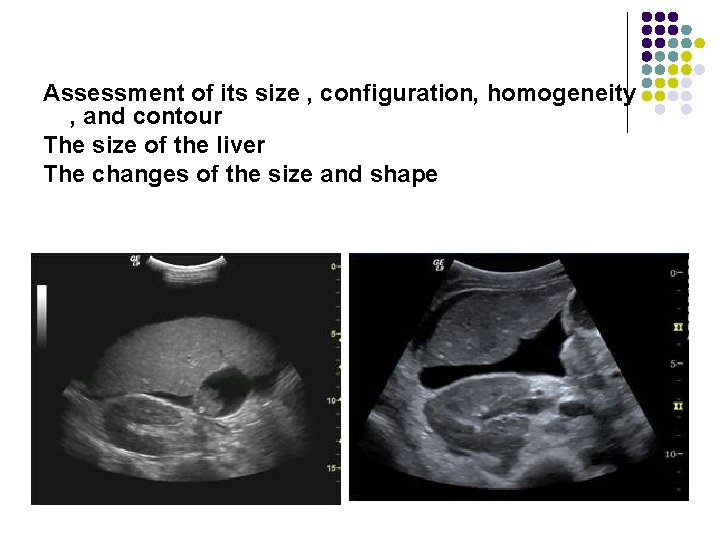

Pathology of the Live l Evaluation of the liver parenchyma includes the assessment of its size , configuration, homogeneity , and contour.

Assessment of its size , configuration, homogeneity , and contour

Assessment of its size , configuration, homogeneity , and contour The size of the liver The changes of the size and shape